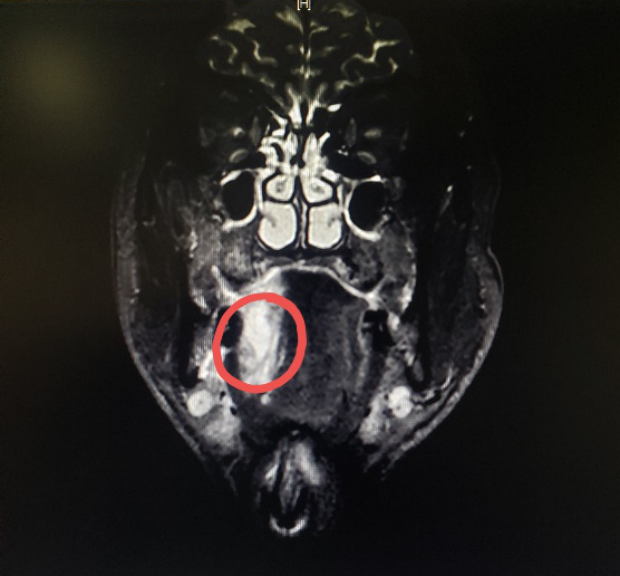

图一:患者的MRI

图二:患者的MRI

图三:患者的MRI